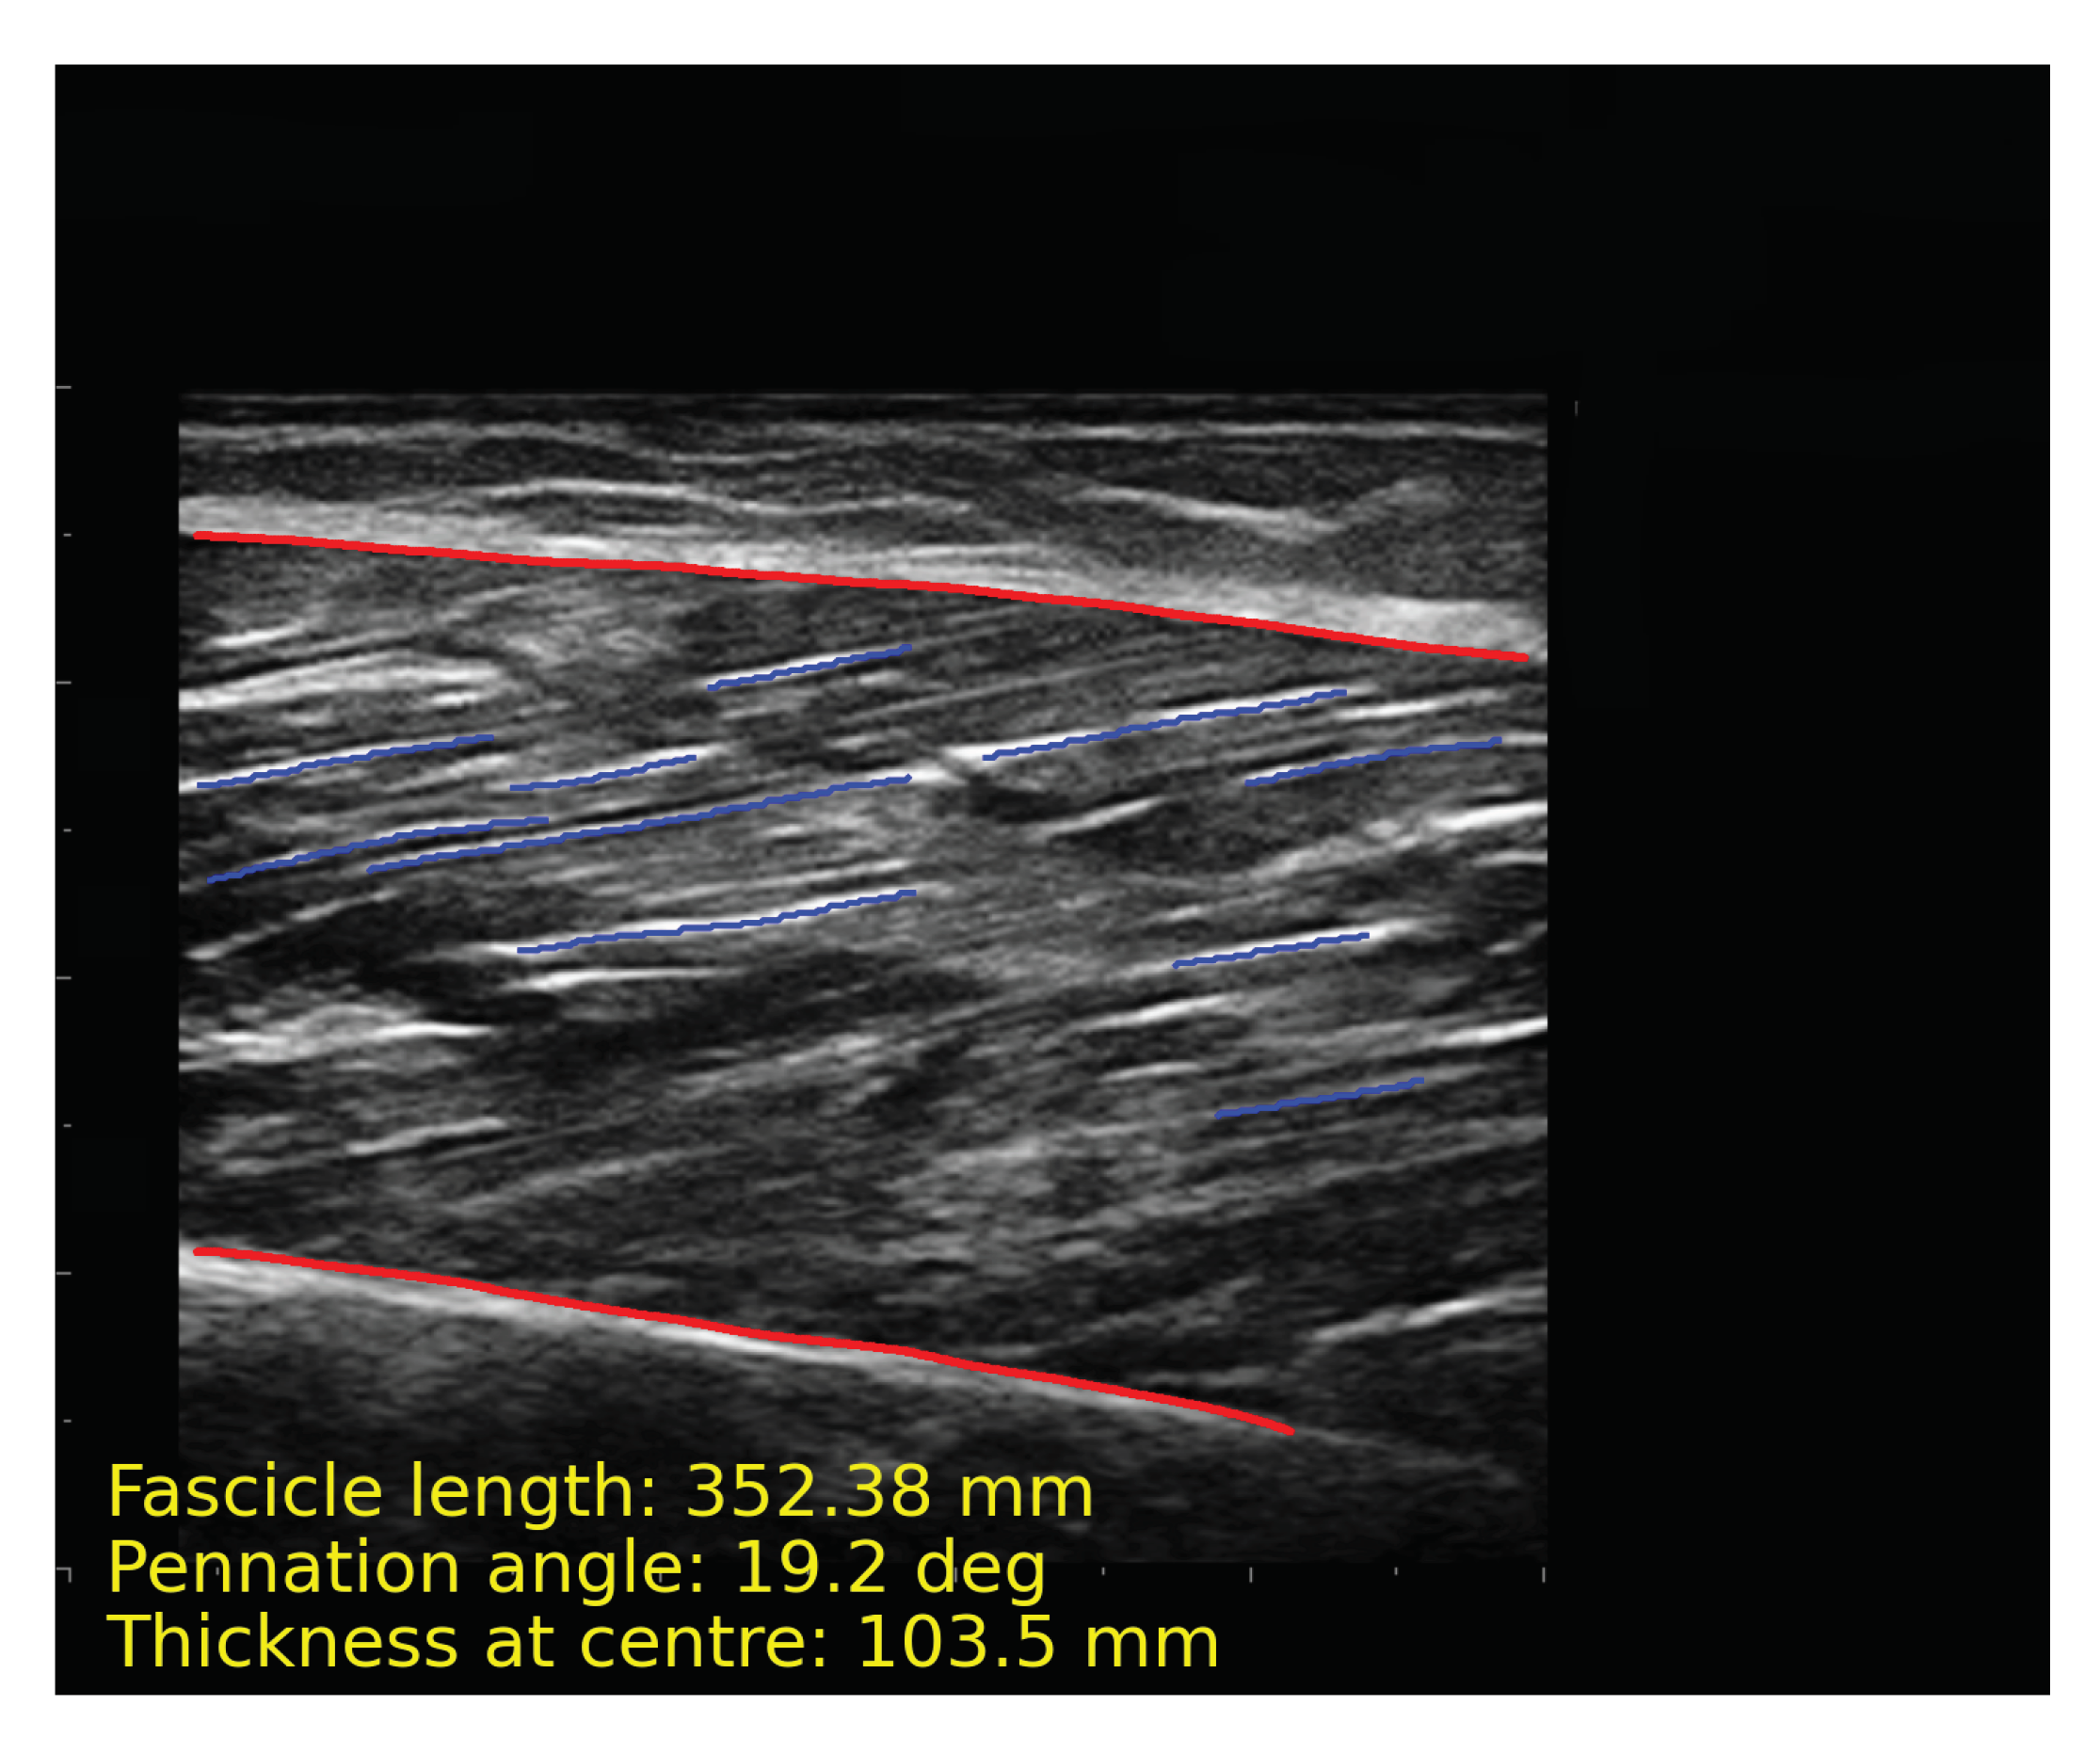

After obtaining the segmentation results of the model, images require a series of post-processing to calculate parameters such as muscle thickness. The following processing is implemented by OpenCv. First, contours of the deep and superficial aponeuroses and fascicles are extracted (Figure 7a). The upper and lower edges of the aponeurosis contours close to fascicles are fitted into a line (Figure 7b). Long fascicles are more accurate and can represent the overall direction of muscle fibers, while the short fascicles are often affected by noise. We selected the 10 fascicles with the longest contours for calculation (Figure 7c). The fascicles were fitted into lines and extended, and intersection points of the fascicles, along with aponeuroses, were calculated. The length and pennation angle of muscle fibers were calculated by taking the average of 10 fascicles (Figure 7d). The muscle thickness is represented by the width at middle of overlapping part of the deep and superficial aponeuroses. The algorithms for calculating muscle thickness, pennation angle and fascicle length are described in Algorithm 1 and Algorithm 2, respectively. Figure 8 shows the final results of post-processing. In order to intuitively display the parameter results, we directly show the parameters in the figure.

Figure 8.

The result of automatic analysis of the muscle ultrasound image. The red line is the contours of aponeuroses, and the blue line is the longest 10 representative fascicles. The calculation results of muscle parameters are displayed at the bottom of the image.